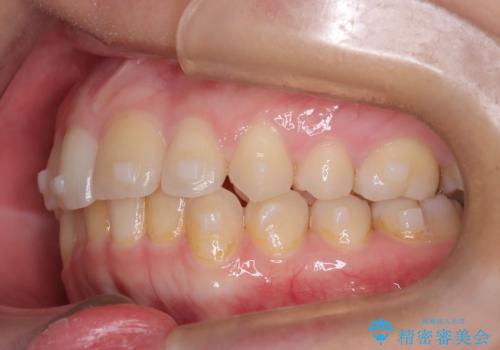

矯正後の後戻り インビザラインで改善

- 前歯のガタツキが気になると来院されました。

マウスピース矯正治療を選択しました。

前歯のガタツキを改善する治療法として、マウスピース矯正が適していることが多いです。

マウスピース矯正は、金属製のブラケットやワイヤーを使用せずに、透明なマウスピースを装着して歯を移動させる方法です。そのため、目立たず、痛みも少ないです。